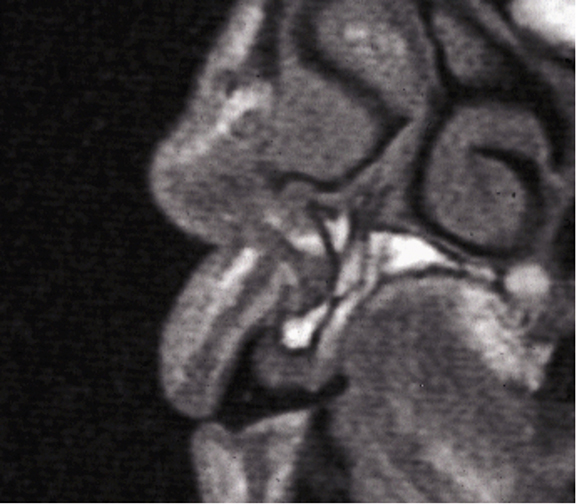

The use of grafting within the mouth can be split into horizontal defects, where the alveolar ridge has been resorbed in width, vertical defects, where the height of alveolus is reduced, and sinus grafting, where there is insufficient vertical bone for implant placement in the maxillary sinus area, and the Schneiderian membrane is elevated, and a graft material is placed within the resulting space [5]. A more recent use is in the treatment of failing implants in peri implantitis cases [6]. Horizontal alveolar defects are more amenable to treatment and have higher success and retention rates than vertical defects. The use of modern imaging techniques such as cone beam computed tomography [7] and magnetic resonance imaging [8] have simplified planning in these cases.

Above: A sectional MRI of the upper incisor area showing loss of horizontal bone requiring grafting.